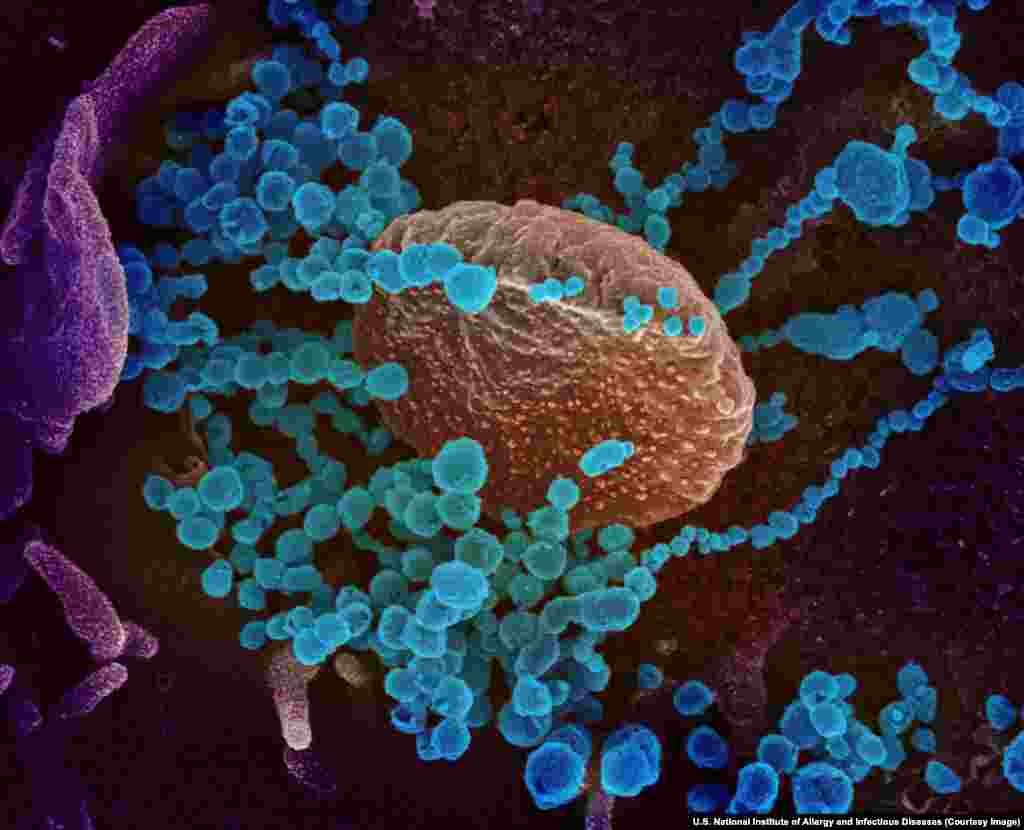

2

Agjentët infektues të koronavirusit që dalin nga qelizat njerëzore. Të gjitha fotografitë në këtë galeri janë ngjyrosur duke përdorur aplikacione si Photoshop, apo të ngjashme.